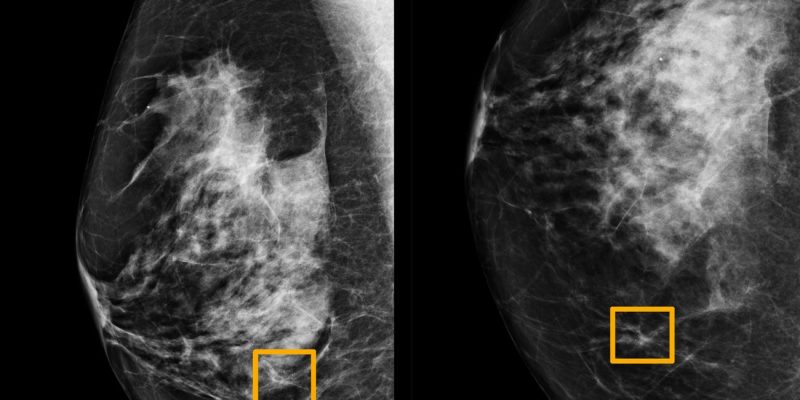

Ακρίβεια ακόμα και μεγαλύτερη από ειδικούς ακτινολόγους στον εντοπισμό του καρκίνου του μαστού έχει ένα σύστημα τεχνητής νοημοσύνης που ανέπτυξε ο τομέας DeepMind της Google, όπως αναφέρουν ερευνητές στις ΗΠΑ και τη Μεγάλη Βρετανία.

Σύμφωνα με την αναφορά των συγκεκριμένων ερευνητών, όπως δημοσιεύτηκε στο περιοδικό Nature πριν από λίγες ημέρες, το ΑΙ σύστημα της Google έχει τη δυνατότητα να βελτιώσει της ανίχνευσης του καρκίνου του μαστού, προσφέροντας υποσχέσεις για τον περιορισμό των λαθών στις διαγνώσεις.

Οι ερευνητές που εργάστηκαν στο συγκεκριμένο project εκπαίδευσαν το σύστημα πάνω σε δεκάδες χιλιάδες μαστογραφίες στις ΗΠΑ και τη Μεγάλη Βρετανία και εν συνεχεία συνέκριναν την απόδοσή του με τα πραγματικά αποτελέσματα από ένα σύνολο σχεδόν 30.000 μαστογραφιών στις δύο χώρες (25.856 στη Μεγάλη Βρετανία και 3.097 στις ΗΠΑ).

Όπως διαβάζουμε, η μελέτη έδειξε ότι το ΑΙ σύστημα μπορούσε να εντοπίσει τους καρκίνους με παρόμοιο βαθμό ακρίβειας με ειδικούς ακτινολόγους, μειώνοντας παράλληλα τον αριθμό των ψευδών θετικών αποτελεσμάτων κατά 5,7% στην ομάδα των ΗΠΑ και κατά 1,2% στην ομάδα που εδρεύει στη Βρετανία. Αντίστοιχα, μείωσε τον αριθμό των ψευδών αρνητικών, κατά 9,4% στις ΗΠΑ και κατά 2,7% στη Μεγάλη Βρετανία.

Σε ένα ξεχωριστό τεστ, οι ερευνητές συνέκριναν ξεχωριστά το ΑΙ σύστημα με τις διαγνώσεις έξι ακτινολόγων, με τα αποτελέσματα να δείχνουν ότι το ΑΙ σύστημα ήταν ακριβέστερο στον εντοπισμού του καρκίνου.

Αξίζει να σημειώσουμε ότι σύμφωνα με την αμερικανική εταιρεία καρκίνου οι ακτινολόγοι χάνουν περίπου το 20% των καρκίνων του μαστού στις μαστογραφίες.